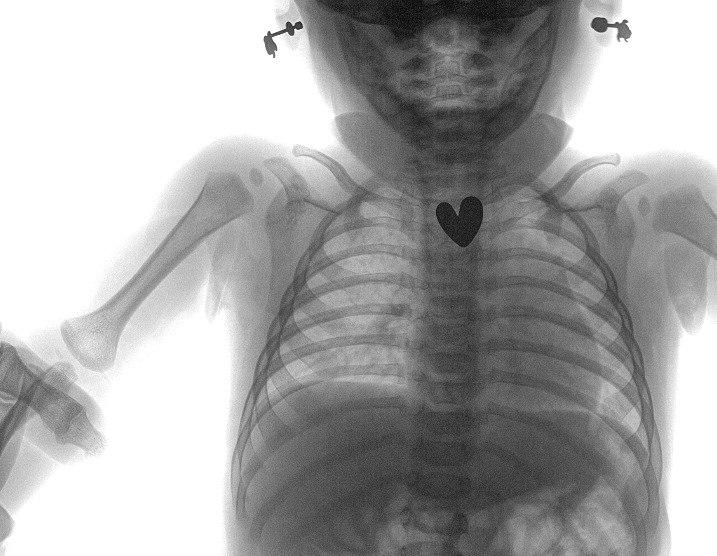

Ему сделали рентген-снимок и в верхней области пищевода обнаружили инородное тело — серёжка в форме сердца размером 1,5 см. Ребенка госпитализировали в хирургическое отделение, провели исследование пищевода, желудка и начального отдела кишечника.

Поскольку серёжка-гвоздик имела острый наконечник и сердцевидную форму, ее спустили в желудок, чтобы избежать травм.